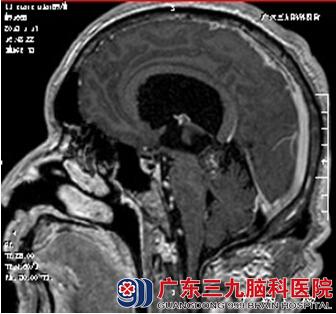

入院后完善相关的检查,头颅磁共振检查示:脑干海绵状血管瘤。完善术前准备,全麻下行 “脑干海绵状血管瘤切除术”。术中肿瘤全切除。术后李先生恢复较好,无明显头晕、头痛,未遗留术后并发症。术后病理提示:海绵状血管瘤。

影像学上表现:磁共振是脑海绵状血管瘤具有较高的诊断的特异性和敏感性 。海绵状血管瘤的磁共振表现有两大特点:①瘤巢中心的血栓和反复出血,内含游离稀释的正铁血红蛋白(MHB),在所有成像序列中均呈高信号;② 血栓与出血灶外周形成的含铁血黄素环在所有成像序列上郁是黑色低信号,且T2上最明显。